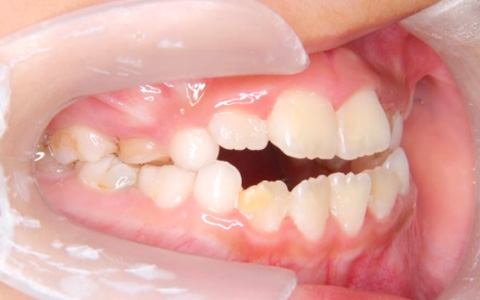

3下顎前突(手術を伴う外科的矯正治療)

主訴:受け口の見た目を治したい(患者年齢:21歳5か月)

診断名:骨格性下顎前突症

治療に用いた主な装置:マルチブラケット装置

抜歯部位:非抜歯

治療期間:2年6か月

治療費概算およびリスク副作用:当科で設定している治療費に準じ、リスク副作用についても日本矯正歯科学会Hp掲載内容を説明(上記参照)

初診時